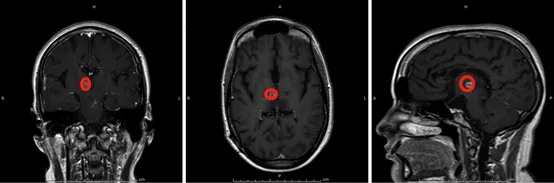

术前脑部磁共振成像MRI显示右侧丘脑增强肿瘤